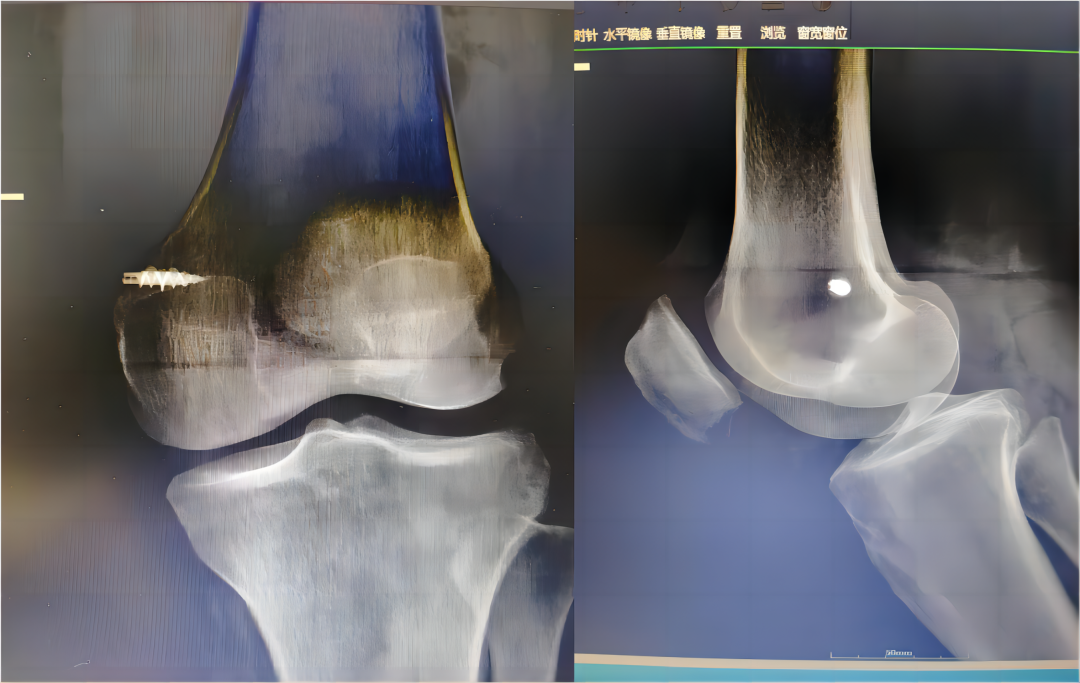

隨著醫(yī)學(xué)的不斷發(fā)展,骨科的部分手術(shù)也一改往日的“粗放”開刀,向微創(chuàng)化發(fā)展。近日,一老年女性患者劉某,因外傷致左膝腫痛入院,經(jīng)詳細(xì)查體,結(jié)合MRI檢查,考慮左膝關(guān)節(jié)內(nèi)側(cè)副韌帶斷裂、前交叉韌帶損傷、半月板損傷及股骨外側(cè)髁損傷。膝關(guān)節(jié)損傷如治療不當(dāng)易導(dǎo)致膝關(guān)節(jié)嚴(yán)重功能障礙,影響生活質(zhì)量。 術(shù)? 前 入院后,科主任魏國華帶領(lǐng)關(guān)節(jié)骨科醫(yī)師團(tuán)隊完善檢查,深入探討,科學(xué)制定手術(shù)方案,決定行內(nèi)側(cè)副韌帶重建及關(guān)節(jié)鏡下膝關(guān)節(jié)探查清理術(shù),術(shù)后患者膝關(guān)節(jié)功能恢復(fù)良好。 術(shù)? 中 術(shù) 后 關(guān)節(jié)鏡手術(shù)是將具有照明裝置的透鏡金屬管通過很小的切口插入關(guān)節(jié)腔內(nèi),將關(guān)節(jié)腔的內(nèi)部結(jié)構(gòu)放大,觀察關(guān)節(jié)腔內(nèi)的病變情況及部位,在監(jiān)視器下進(jìn)行全面檢查和清理病損部位,開展鏡下手術(shù)操作。作為一種微創(chuàng)手術(shù)同時具有診斷和治療兩種功能,相比傳統(tǒng)手術(shù)具有創(chuàng)傷小、出血少,恢復(fù)快、診斷準(zhǔn)、操作精、處理全、外觀美等優(yōu)點(diǎn),是骨科理想的診斷與微創(chuàng)手術(shù)治療方式。 主要用于治療膝、肩關(guān)節(jié)的常見疾?。喝绻切躁P(guān)節(jié)炎、滑膜炎、關(guān)節(jié)內(nèi)游離體、半月板損傷、交叉韌帶損傷、肩周關(guān)節(jié)炎、凍結(jié)肩、肩峰撞擊癥、肩袖損傷等。 就診科室:酒泉市中醫(yī)醫(yī)院關(guān)節(jié)骨科 就診地點(diǎn):門診樓:205室,電話0937-2669113 住院部:綜合樓6樓,電話0937-2620311